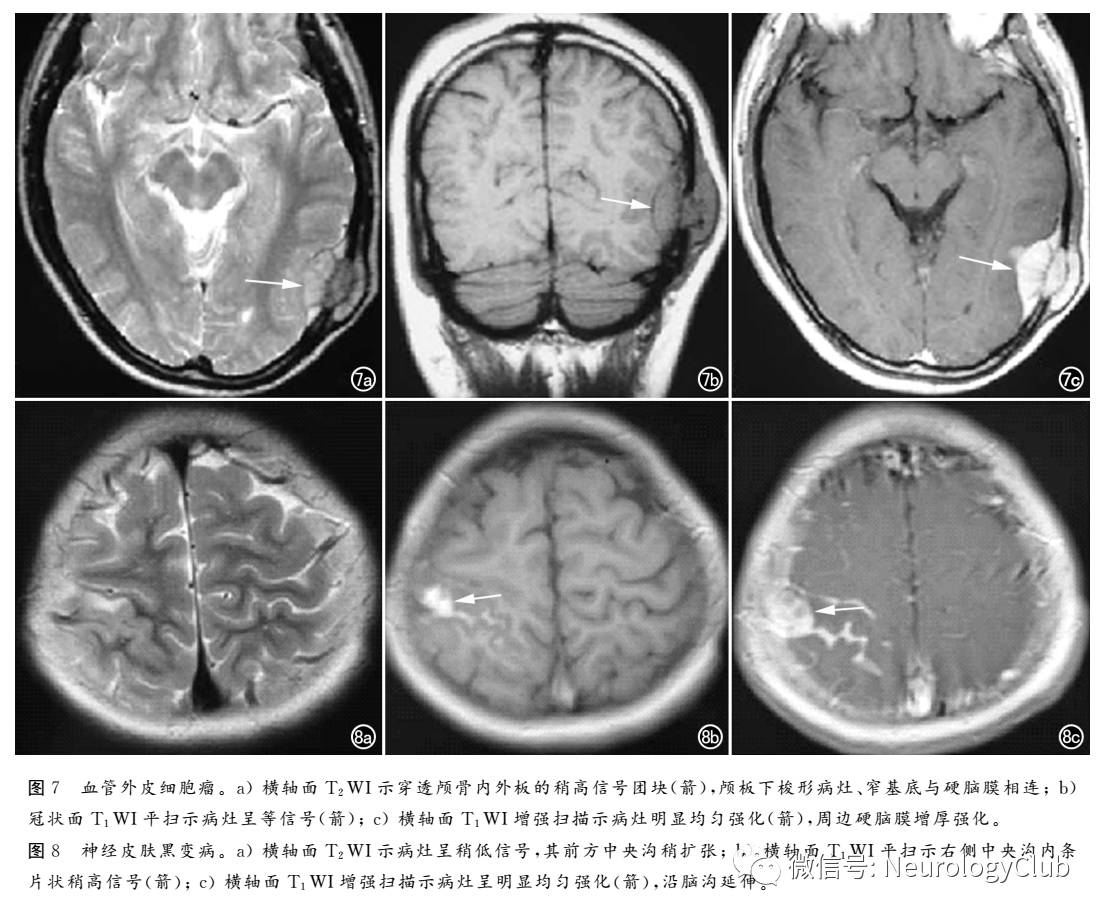

血管外皮细胞瘤,来源于脑膜间质组织的毛细血管壁的周细胞,又称为血管周细胞瘤,WHO分级II-III级,大部分血管外皮细胞瘤实性部分T1WI呈等或略低信号,T2WI呈等或略高信号,囊变坏死部分呈长T1、长T2信号。增强扫描病变实性部分及血管明显强化(图7)。肿瘤可表现为分叶征,以窄或宽基底与硬脑膜相连,血管丰富,易出血、坏死致信号不均匀,可破坏邻近颅骨,但无反应性增生肿瘤邻近脑实质受压,可见“白质塌陷征”

弥漫性黑色素细胞增生症是一种十分罕见的神经皮肤综合征,表现为原发性脑膜弥漫性或局限性肥厚和色素沉着,并伴有巨大皮肤黑色素痣MRI表现为脑脊膜增厚,T1WI上信号强度增强,MRI增强扫描对脑膜黑色素瘤的诊断有一定价值,常表现为弥漫性或局灶性软脑膜或硬脑膜强化、脑积水以及脑组织表面的小瘤灶(图8)。